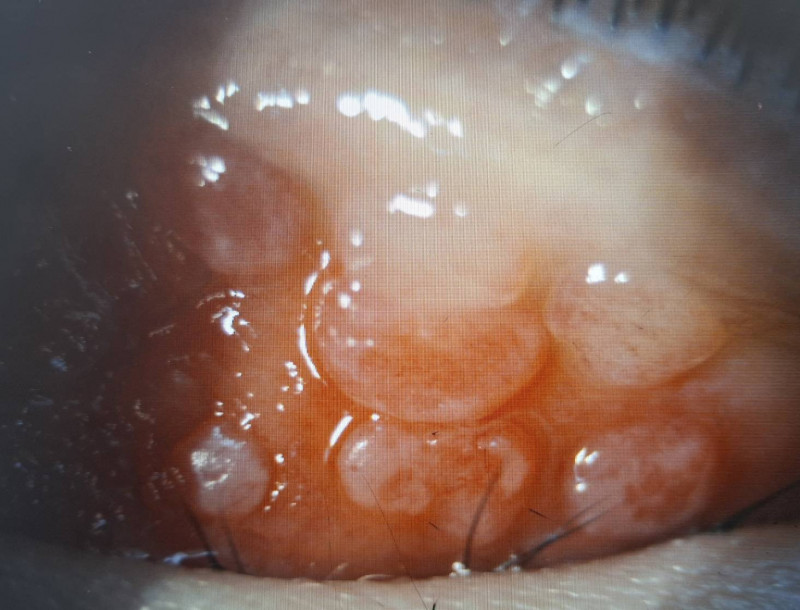

男童因結膜慢性發炎,使結膜上皮細胞的過度增生,長成大於0.1公分的乳突。(洪啟庭提供)

巨大乳突壓迫不僅造成角膜潰瘍,還出現高度散光而視力模。(洪啟庭提供)

達特楊眼科聯盟執行長洪啟庭指出,小二男童就醫時不僅左眼眼瞼嚴重腫脹,最佳視力僅0.5並有300度散光,應是過敏性結膜炎合併過敏性鼻炎、濕疹、異位性皮膚炎或氣喘等,因為長期揉眼導致眼皮長滿巨大乳突,因長時間壓迫造成上半部角膜有淺層潰瘍,故造成300度的高度散光和視力模糊,經強效抗生素與適當類固醇藥水治療,2星期後角膜潰瘍痊癒,乳突的也變小,學童眨眼睛的現象也明顯改善,但乳突完全消失恐要半年以上。